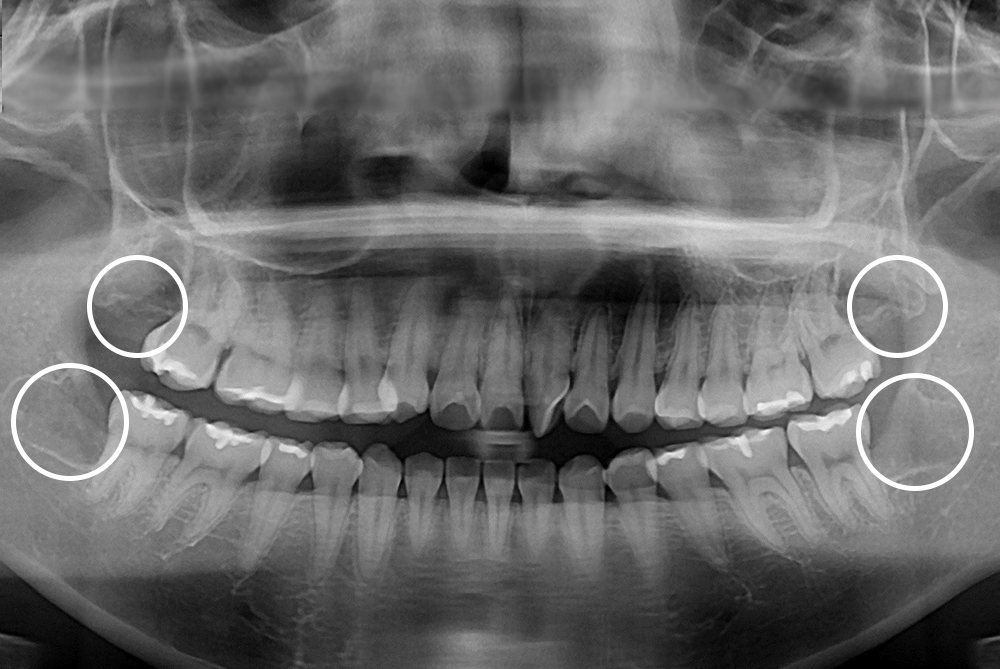

[사랑니] 매복 사랑니 발치

치료전 : 2018-09-13

세종치과는 구강악안면외과학 박사이신 원장님이 발치하는 치과입니다.